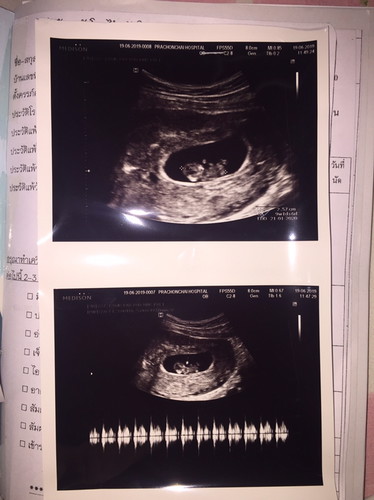

ดูน้ำหนักเจ้าตัวน้อยตรงไหนคะ

สอบถามแม่ๆจ้า ดู นน. เจ้าตัวน้อยตรงไหนคะ

ถูกต้องตามเม้นด้านล่างเลยค่ะคุณแม่ ช่วงแรก คุณหมอจะวัดแค่ขนาดตัวนะคะ พอเข้าไตรมาส 2 นน จะเริ่มมีความสำคัญในการประเมินสุขภาพลูกน้อยมากกว่าความยาวค่ะ

ในนี้บอกแค่ขนาดค่ะ 8 cm น่าจะยังตัวเล็กอยู่นะคะ จึงไม่สามารถคำนวนน้ำหนักได้ค่ะ

ใบซาวด์ตัวนี้ไม่มีบอกค่ะ ต้องถามคุณหมอเอง